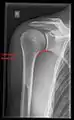

Shoulder imaging

Imaging of the shoulder includes ultrasound, X-ray and MRI, and is guided by the suspected diagnosis and presenting symptoms.

Conventional x-rays and ultrasonography are the primary tools used to confirm a diagnosis of injuries sustained to the rotator cuff. For extended clinical questions, imaging through Magnetic Resonance with or without intraarticular contrast agent is indicated.

Hodler et al. recommend starting scanning with conventional x-rays taken from at least two planes, since this method gives a wide first impression and even has the chance of exposing any frequent shoulder pathologies, i.e., decompensated rotator cuff tears, tendinitis calcarea, dislocations, fractures, usures, and/or osteophytes. Furthermore, x-rays are required for the planning of an optimal CT or MR image.[22]

X-ray

Projectional radiography views of the shoulder include:

- AP-projection 40° posterior oblique after Grashey

The body has to be rotated about 30 to 45 degrees towards the shoulder to be imaged, and the standing or sitting patient lets the arm hang. This method reveals the joint gap and the vertical alignment towards the socket.[23]

- Transaxillary projection

The arm should be abducted 80 to 100 degrees. This method reveals:[23]

- The horizontal alignment of the humerus head in respect to the socket and the lateral clavicle in respect to the acromion

- Lesions of the anterior and posterior socket border, or of the tuberculum minus

- The eventual non-closure of the acromial apophysis

- The coraco-humeral interval

- Y-projection

The lateral contour of the shoulder should be positioned in front of the film in a way that the longitudinal axis of the scapula continues parallel to the path of the rays. This method reveals:[23]

- The horizontal centralization of the humerus head and socket

- The osseous margins of the coraco-acromial arch and hence the supraspinatus outlet canal

- The shape of the acromion

This projection has a low tolerance for errors and, accordingly, needs proper execution.[23] The Y-projection can be traced back to Wijnblath’s 1933 published cavitas-en-face projection.[24]

CR. shoulay film.